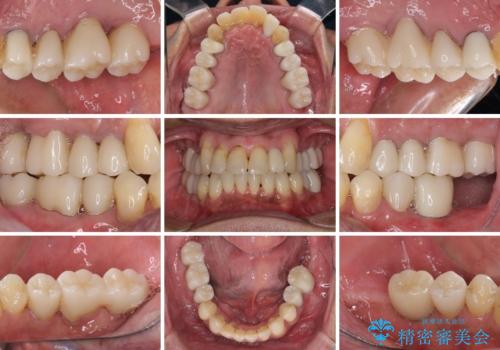

- 前歯がのデコボコや、奥歯に咬んだときに痛みがあるとのことで来院された患者様です。

全体的に問題が多く、全てをしっかりと治療したいとのことでした。

全体的に中等度の歯周病と診断されたため、歯周外科処置やインプラントによる咬合回復から進めて行き、矯正治療による歯列改善を行った後にオールセラミッククラウンにて補綴することとしました。

歯槽骨の再生治療を行ったため、外科処置後の静置期間がながくなり、4年弱の治療期間となりました。

初診来院時には矯正治療を行うことは想像していなかったようで、治療後には咬みやすさだけでなく、前歯が大変審美的に仕上がり、患者様には大変満足していただきました。